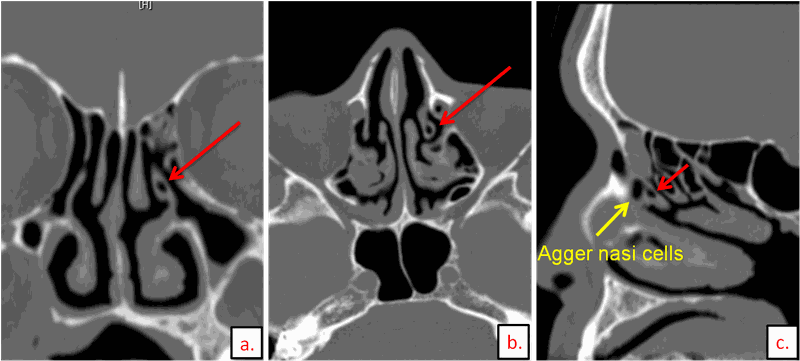

Chụp CT xoang mũi là kỹ thuật sử dụng tia X để quét vùng đầu mặt theo lát cắt ngang, sau đó xử lý bằng máy tính để tạo ra hình ảnh 2D hoặc 3D chi tiết của hốc xoang mũi.

Chụp CT xoang mũi được sử dụng để phát hiện và chẩn đoán các bệnh lý như viêm xoang và khối u trong các hốc xoang mũi, cụ thể:

• Viêm xoang: Chụp CT được đánh giá là phương pháp chẩn đoán viêm xoang chính xác hơn so với chụp X-quang.

• Ung thư lan vào xoang bướm: Chụp CT có thể cho thấy rõ hình ảnh thành trước xoang bướm bị phá hủy.

• Ung thư lan vào xoang hàm: Chụp CT hiển thị hình ảnh thâm nhiễm của ung thư vào xoang hàm.

• Ung thư lan vào màng não cứng và não: Chụp CT có thể phát hiện sự ăn mòn và phá hủy mảnh sàng do khối u gây ra.